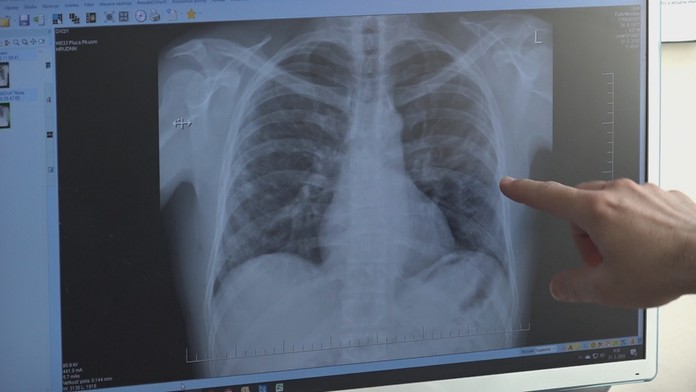

Po Európe sa šíri nepríjemná baktéria. Spôsobuje zápal pľúc, najmä u mladých ľudí

Baktéria, ktorá môže spôsobiť rôzne respiračné ochorenia, je odolná voči mnohým antibiotikám.

V krajinách Európy sa rýchlo šíria takzvané mykoplazmy. Upozornil na to web tn.cz. Ide o baktérie, ktoré môžu spôsobiť zápal pľúc či ďalšie respiračné ochorenia.

Tie sa šíria najmä medzi mladými ľuďmi do 30 rokov. „Nárast prípadov je pomerne značný, v niektorých krajinách až päťnásobný,“ hovorí epidemiológ Roman Prymula.

Mykoplazmy sa prenášajú sa vzduchom alebo priamym kontaktom s infikovaným človekom. Dôležitá je prevencia.

Ak však už dôjde k nákaze, ochorenia spôsobené mykoplazmami sa liečia antibiotikami. Voči niektorým sú však odolné.

Podľa Anny Frogáčovej, lekárky ambulancie pneumológie a ftizeológie Nemocnice AGEL Levice, treba liečbu dodržiavať podľa pokynov lekára.

„Pri nedodržaní liečby, respektíve bez antibiotík sa môže doba liečenia predĺžiť,“ uviedla.